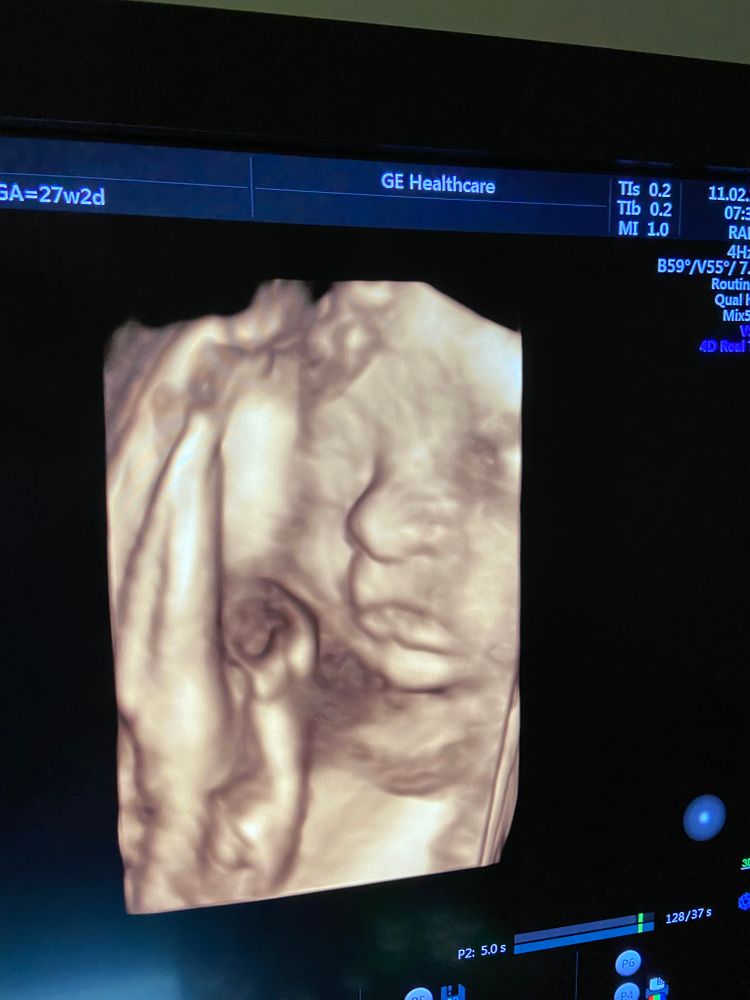

11 февраля 27 недель 2 дня очередное узи с 3д

Все хорошо, малышка подросла, изменилась в лице. Активно зевала и корчила личико. Главное здорова.